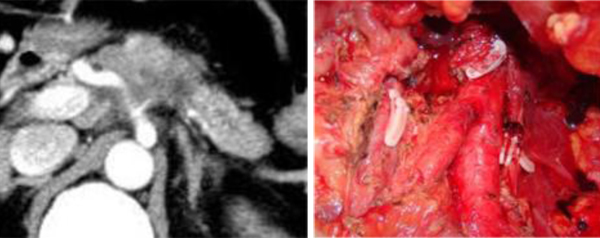

Surgery for Biliary Cancer Using Image-Guided Navigation

Radical surgery is essential for the treatment of biliary cancer. The surgical approach varies depending on the tumor’s location. In cases of hilar cholangiocarcinoma, extensive liver resection is necessary, requiring advanced medical techniques. In addition to accurately assessing the extent of cancer progression for radical surgery, precise preoperative imaging is crucial.

To perform biliary cancer surgeries with high safety and radicality, we utilize image-guided navigation to precisely simulate the bile duct resection site. Our hepatobiliary-pancreatic surgery team holds detailed conferences to determine the optimal surgical approach, ensuring that the surgery is performed with precision.